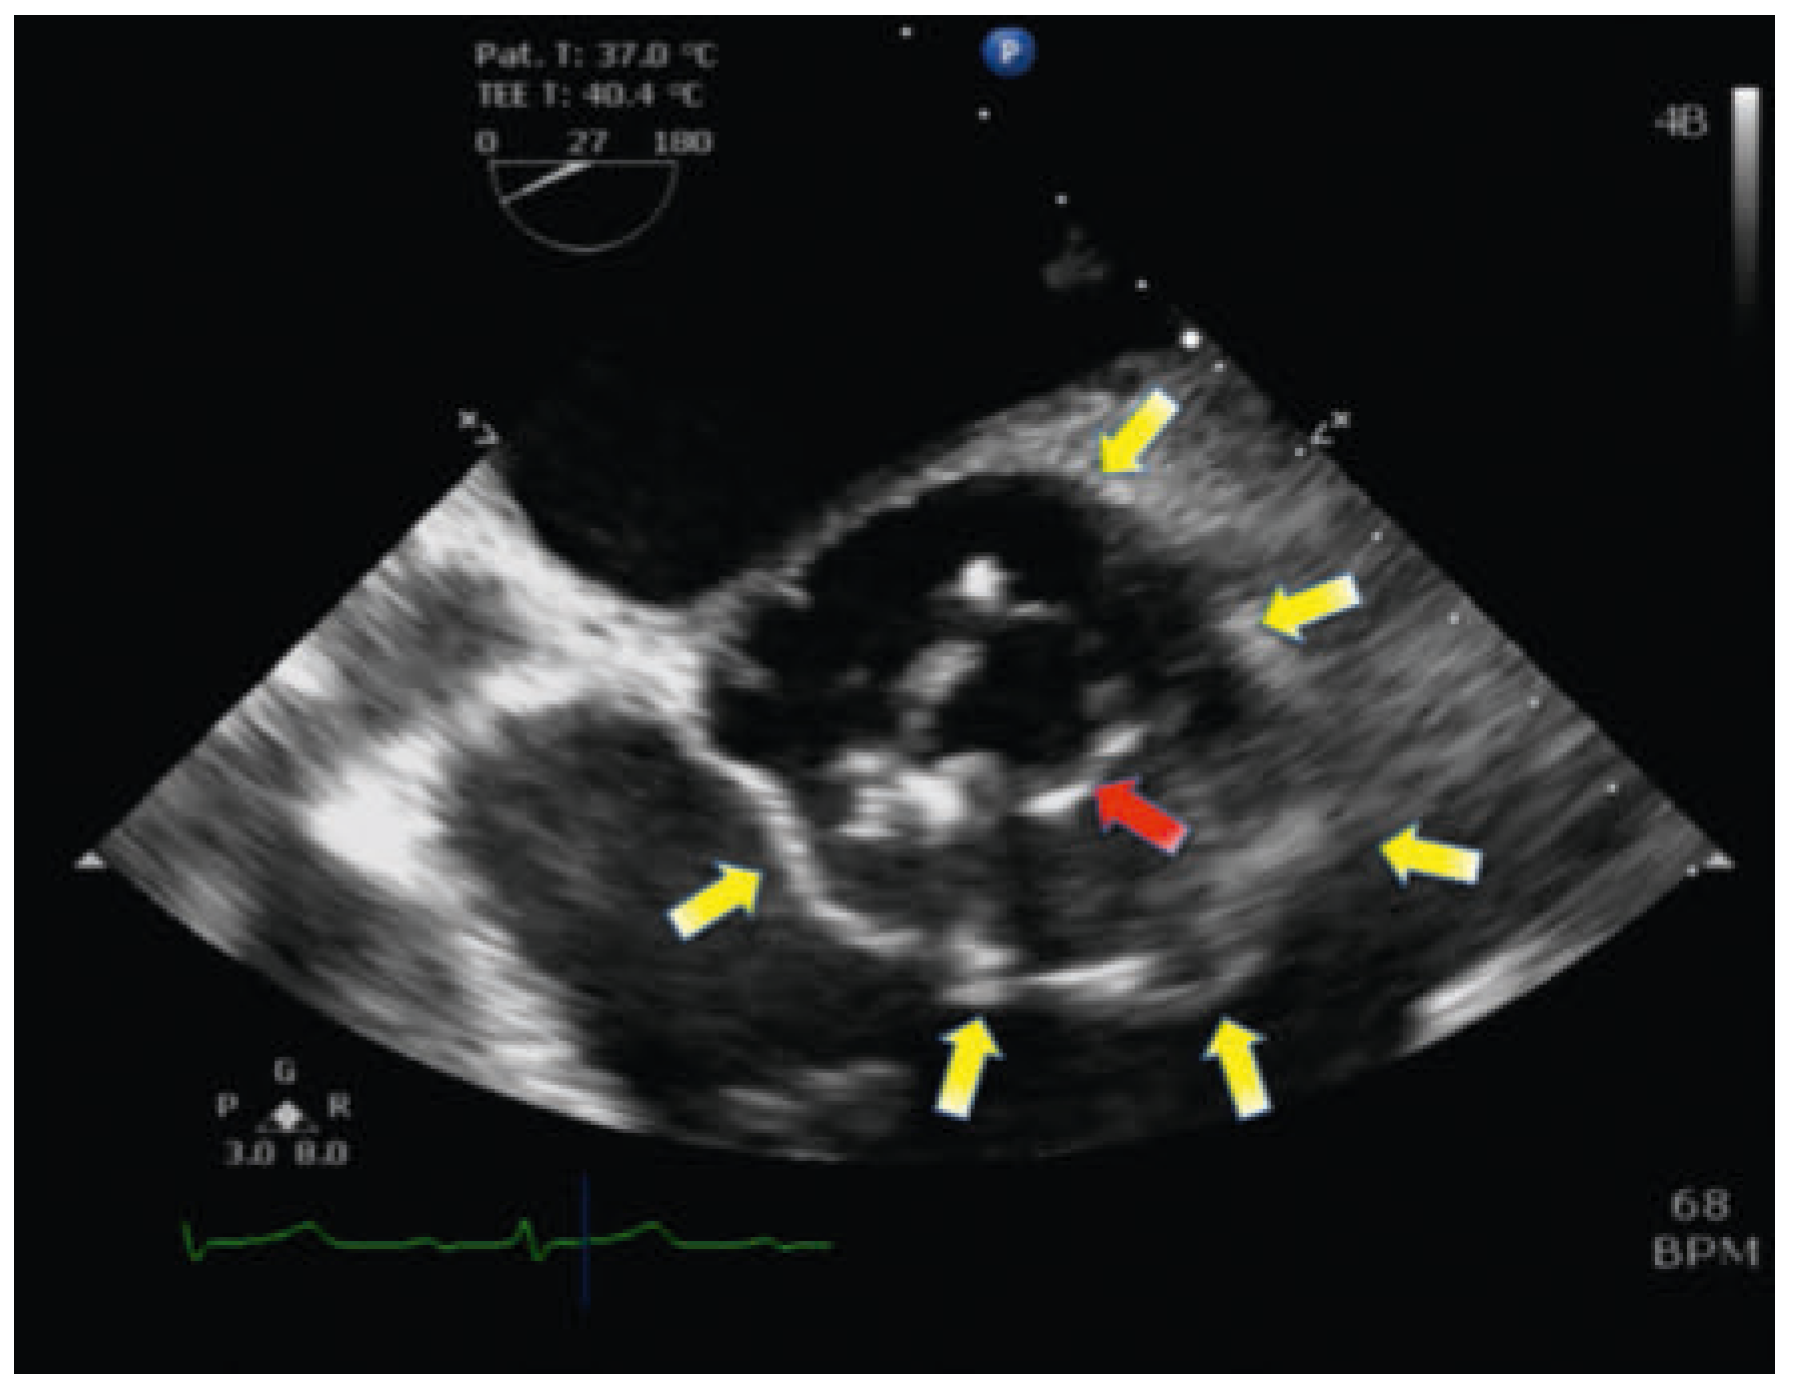

One year later, in June 2014, the patient received an en-doprosthesis of the left knee because of the severe arthrosis. Cefazolin was administered as intraoperative prophylaxis. Initially, the postoperative course was uneventful; specifically, there was no need of antibiotic treatment. In December 2014, the patient presented again with a swelling of the left knee and fever. As a patient at high risk for endocarditis after valve replacement and endoprosthesis implantation, a TTE was performed immediately on admission and a TOE 2 days later, without signs of an abscess, vegetation or perforation and with a competent aortic valve prosthesis. Empirical therapy was started with vancomycin and ciprofloxacin on the admission day. Three days after the negative TEE, the patient was scheduled for lavage of the knee prosthesis and a change of the inlay for eradication of the local infection. Twelve days later a second TOE was indicated because of persistent inflammation under antibiotic therapy. Clinically, there was no sign of cardiac decompensation or any cardiopulmonary symptoms. The echocardiographic findings were a vegetation of 0.8 cm on the aortic valve prosthesis and a new periannular abscess (Figure 1). The ECG did not show any abnormalities due to the annular abscess and, especially, no signs of atrioventricular block. The analysis of the blood cultures and knee aspirate confirmed S. pneumoniae. Antibiotic therapy was changed to ceftriaxone complemented by rifampicin and gentamicin after diagnosis of the valve vegetation. Because of suspected endocarditis, transfer to the cardiac surgery department was organised.

Figure 1. TOE on second admission to cardiac surgery during relapse after implantation of knee prosthesis: annular abscess (yellow arrow) around the prosthetic valve (red arrow).